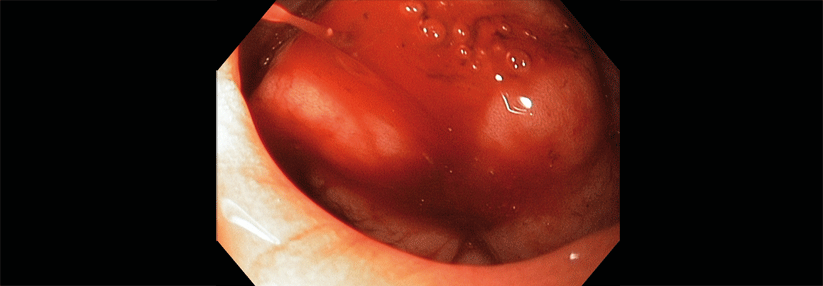

Patienten mit einer eingeschränkten Nierenfunktion (GFR < 50 ml/min.), einem Lebensalter über 75 Jahre sowie einem niedrigen Körpergewicht (< 50 kg) gelten als „fragil“. Sie weisen ein erhöhtes Risiko für Schlaganfälle und Blutungen auf. Das macht es nicht einfach, die richtige Antikoagulation für sie zu finden.